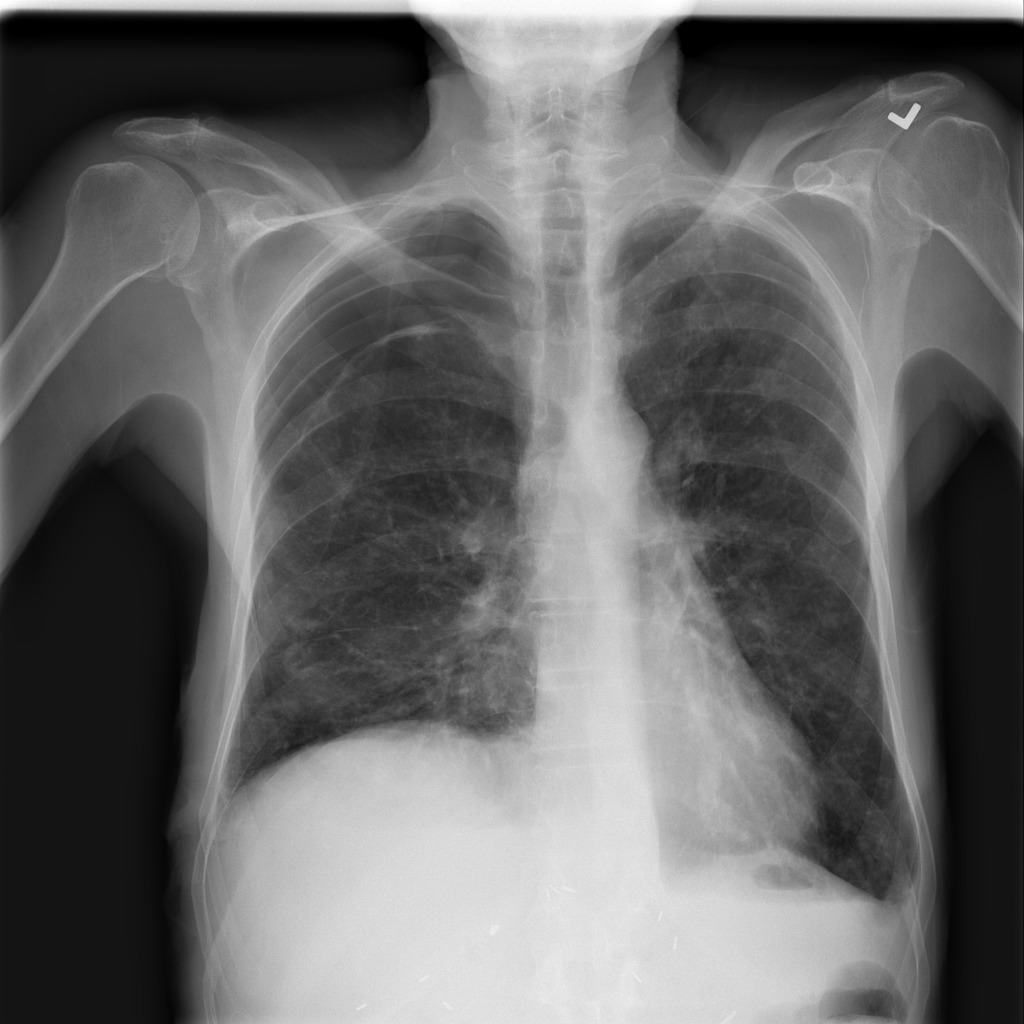

Refer to caption

(a) Image

Figure 1: Pneumothorax localization maps for (a) a random image from the test set at each consecutive step of our method: (b) map after CAM extraction, (c) improved map by IRNet trained on the outcomed of step 1, (d) prediction of U-Net trained on step 2 results, all compared to (e) ground truth mask.

We present method’s explainability via disease localization regions; cf. Figure 1. We provide qualitative results of segmentation on validation images from both datasets in Figure 2 and Figure 3. We show the resulting maps at each step of our method; the figures demonstrate how the performance improves after each step. We achieve comparable results to state-of-the-art method on PASCAL VOC 2012; cf. Table 4.